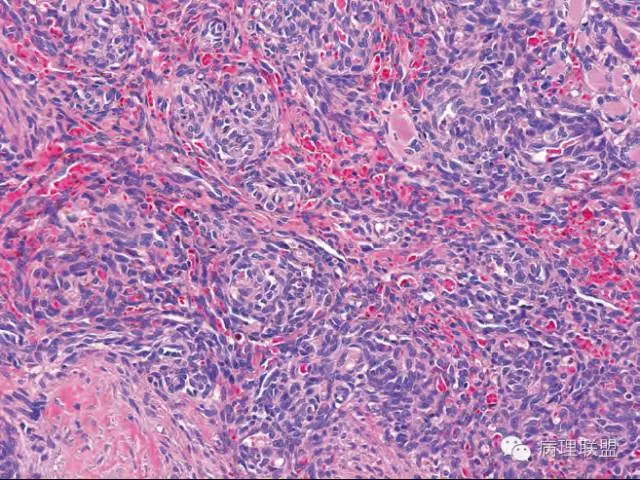

Kaposi型血管内皮瘤常有隐约小叶结构,梭形细胞束间有毛细血管,细胞核异型性和分裂活性一般不明显,常见梭形细胞束和圆形"肾小球样"实性细胞巢混合存在。

有些区域类似Kaposi肉瘤,如下图

而复合性血管内皮瘤则是由良性、中间性和恶性的成份组成,也是浸润性生长,常常侵犯皮下脂肪组织,此例细胞形态由梭形细胞、卵圆形细胞及上皮样细胞组成,形态可见良性区域、中间性区域及高分化血管肉瘤或上皮样血管肉瘤区域,因此,似乎复合性血管内皮瘤更妥。此类肿瘤可以发生于婴幼儿。当然与Kaposi型血管内皮瘤一样,同属中间性血管瘤,只是后者,若肿瘤体积大,可出现Kasabach-Merritt综合征。

这种形态若在老年人头面部就是血管肉瘤,而在婴幼儿就降级了。